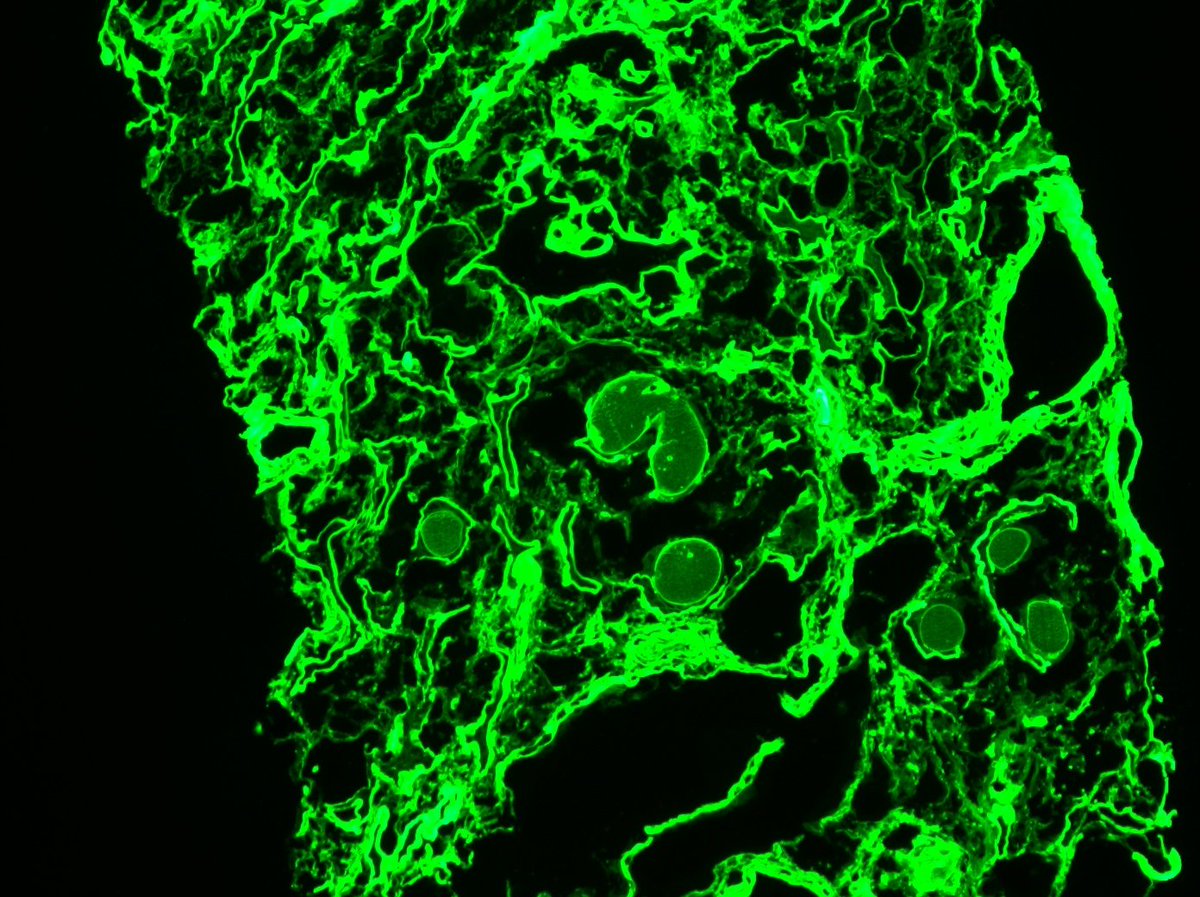

Long weekend often brings urgent cases. Here is one that was STATed, ended up showing anti-GBM GN. Diffuse crescents (nearly 100%). Linear IgG. #RenalPath